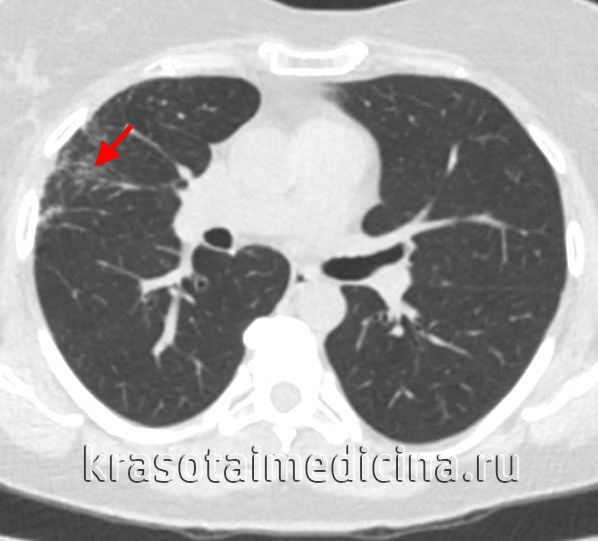

- Рентгенография и КТ лёгких. На рентгенограмме заметны усиление и деформация лёгочного рисунка, фокусы инфильтрации в проекции зоны облучения, плевральный выпот. Одностороннее поражение является патогномоничным признаком заболевания. КТ позволяет раньше выявить и более точно определить границы повреждения.

КТ органов грудной клетки. Снижение пневматизации в периферических отделах правого легкого после лучевой терапии по поводу рака молочной железы.

Дополнительно выполняется исследование газового состава крови и функции внешнего дыхания. В неясных случаях для уточнения диагноза используется МРТ. Постлучевой пневмонит следует дифференцировать с метастатическим обсеменением, бактериальной пневмонией, а также с туберкулёзом и микозами, которые могут быть спровоцированы вторичным иммунодефицитом.